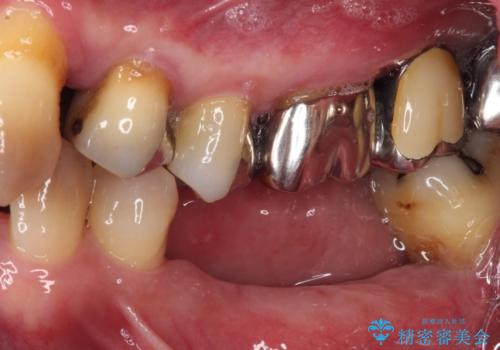

強い咬合力で奥歯がボロボロに インプラント治療による咬合回復と全顎セラミック治療

- 奥歯が咬みにくく、前歯がぐらぐらするとのことで来院された患者様です。

咬合力が強く、奥歯が欠損している状態でした。

欠損部はインプラントによる補綴治療を行うこととし、臼歯部が安定した後に、上下前歯部をオールセラミッククラウンにて補綴治療を行うこととしました。

上顎前歯に歯周ポケットの深い部分がありましたが、インプラントの仮歯で奥歯がしっかりと噛めるようになると、1年程度で深い歯周ポケットは解消されました。